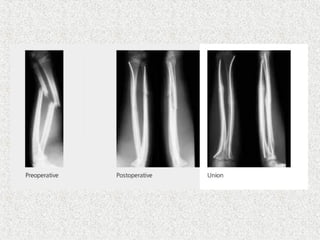

 Closed unstable#  Irreducible #  Polytrauma  Always descending technique  Medial & lateral of tibial tuberosity  Nail tip curved posteriorely-antecurvation